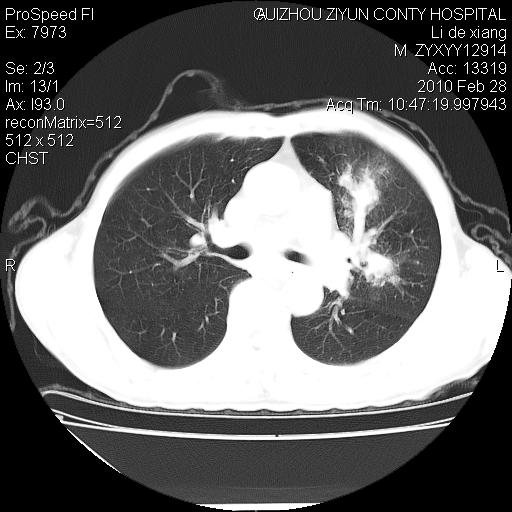

标题: CT24776:男 71Y 咳嗽咳痰胸痛两月,伴声音嘶哑。 [打印本页]

标题: CT24776:男 71Y 咳嗽咳痰胸痛两月,伴声音嘶哑。

左侧中央型肺癌伴左肺上叶阻塞性肺炎及节段性不张可能性大,建议纤支镜检查!

左侧中央型肺癌伴左肺上叶阻塞性肺炎及节段性不张可能性大,建议纤支镜检查!纵隔淋巴结转移.

左肺门部肿块,伴左上肺斑块影,周边模糊,支持左肺中央型肺癌伴节段性不张及阻塞性肺炎,结合支气管镜检查。

左上叶支气管狭窄,阻塞性病变,肺门肿块,纵隔及肺门淋巴结增大,中央性肺癌

左侧中央型肺癌伴左肺上叶阻塞性肺炎及纵隔淋巴结转移

支持 左肺中央型肺癌伴左肺上叶阻塞性肺炎,纵隔淋巴结转移。